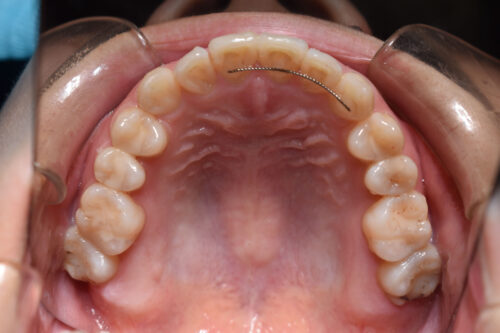

初診時年齢 28歳 女性

歯のでこぼこ(叢生)

下顎右側第一大臼歯欠損(歯をぬいた)

を主訴に

池袋よりひとつ隣駅の東京都豊島区大塚駅すぐの大塚たまみ矯正歯科へ

いらっしゃいました。

歯のがたつき (叢生)

と

受け口が認められました。

本症例も

下顎右側第一大臼歯欠損

上下とも歯が唇側に傾斜し

下の歯が上の歯よりも外にでている 受け口の状態でした。